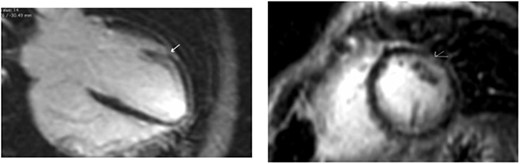

Clinically, both patients complained of worsening palpitations over the last few months with no associated dyspnea or tiredness. A Holter examination recorded 14 444 VES and 212 NSVT, with very similar results in both sisters. The echocardiography revealed a myxomatous Barlow mitral valve with anterior and posterior leaflet prolapse and two regurgitant jets resulting in moderate to severe mitral valve regurgitation as well as mitral annular disjunction in both cases (Figs 1 and 2). A cardiac MRI on a 3 T Lumina Siemens revealed at the mid-left ventricular level, a midwall fibrosis in the midlateral myocardium (Figs 3 and 4) and confirmed a mitral annular disjunction of 12 mm (Figs 5 and 6). Additional findings included a dilated LV with mildly depressed contractility, no visible myocardial scarring, no structural heart disease and a normal sized RV with mildly depressed contractility.

In our reported case, both patients underwent an S-ICD implantation before discharge as they were both considered to have a high risk of sudden cardiac death. The role of ICD implantation as primary prevention in such cases is unclear as available data are limited. We consider an individual risk stratification of such patients appropriate taking into consideration the arrhythmogenic potential of MAD, myocardial fibrosis, medical history of malignant arrhythmias and family history. In our case, both sisters presented with a large longitudinal distance of MAD in magnetic resonance, severe Barlow’s disease at a young age, and a reported case of sudden cardiac death in the family all of which are predictors of arrhythmias in MAD [6]. The choice of subcutaneous ICD implantation vs. transvenous was made solely on the patient’s age and preservation of their quality of life.